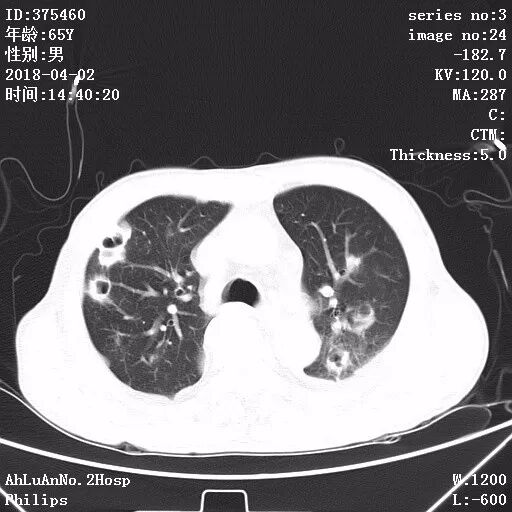

患者男,65岁,因“咳嗽、咳痰1月余,发热1周”入院。

两肺可见多发斑片状及气囊样阴影,部分气囊样影内可见气液平面,两侧胸膜腔可见少量液性密度影聚集。

结果:金黄色葡萄球菌肺炎